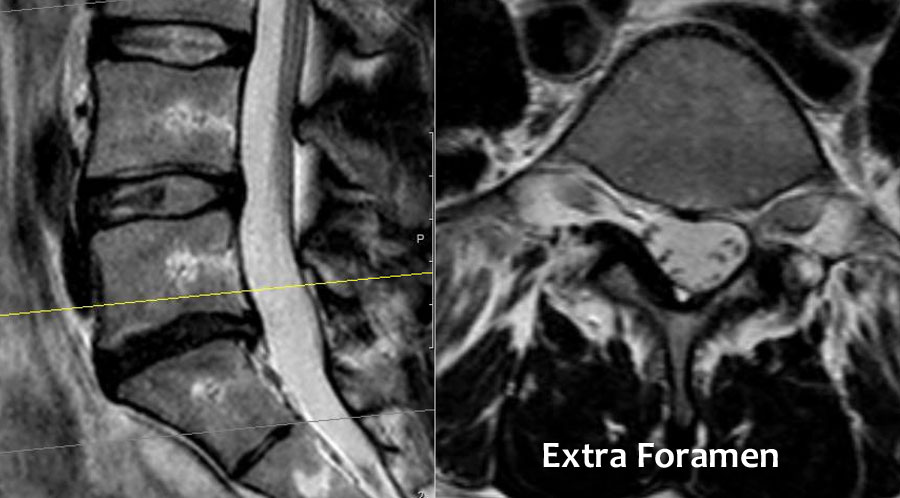

Cuộn qua các hình ảnh để quan sát đường đi của các rễ thần kinh tại mức độ đĩa đệm, ngách bên, lỗ liên hợp và ngoài lỗ liên hợp.

Tại mỗi mức độ có thể thấy các bệnh lý đặc trưng, nhưng có sự chồng lấp đáng kể.

Ví dụ, đĩa đệm có thể thoát vị và gây chèn ép thần kinh tại mức độ đĩa đệm, nhưng cũng có thể di trú xuống tầng thấp hơn và chèn ép rễ thần kinh trong ngách bên, hoặc di chuyển lên trên và gây chèn ép tại mức độ lỗ liên hợp hay ngoài lỗ liên hợp.

Hẹp lỗ liên hợp được gặp trong thoái hóa khớp mỏm khớp, trượt đốt sống và thoát vị đĩa đệm trong lỗ liên hợp – thường là đĩa đệm di trú từ tầng thấp hơn. - Ngoài lỗ liên hợp.

Đây là vùng nằm bên ngoài lỗ liên hợp.

Chèn ép thần kinh tại vùng này không phổ biến, nhưng đôi khi do thoát vị đĩa đệm sang bên gây ra.